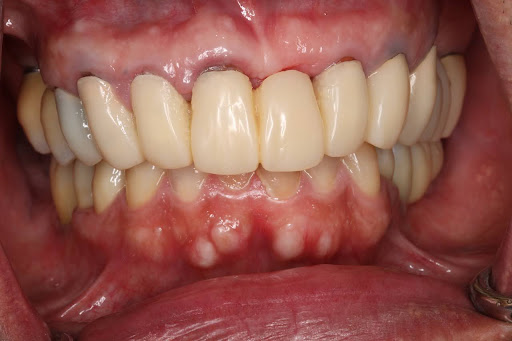

症例